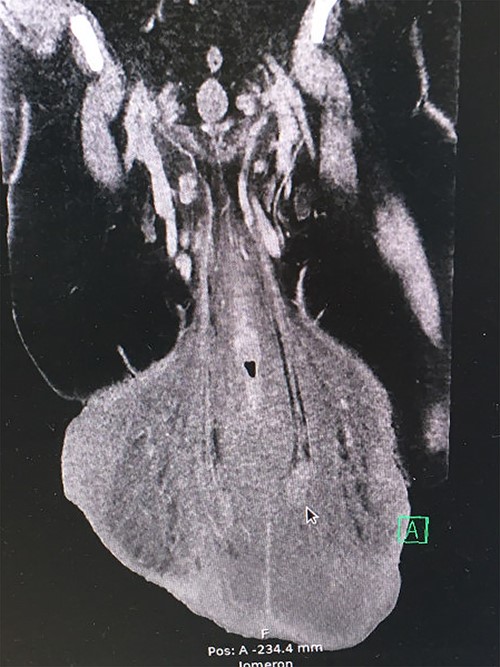

The preoperative computed tomography (CT) scan showed enlarged lymph nodes along the iliac vessels bilaterally and in the groin. Apart from massive edema that had increased more than 10-fold in volume over 2 years, it revealed a network of enlarged veins and intact testicles at the end of a 17-cm long furnicle with no radiological signs of malignancy or herniation (Fig. 3).